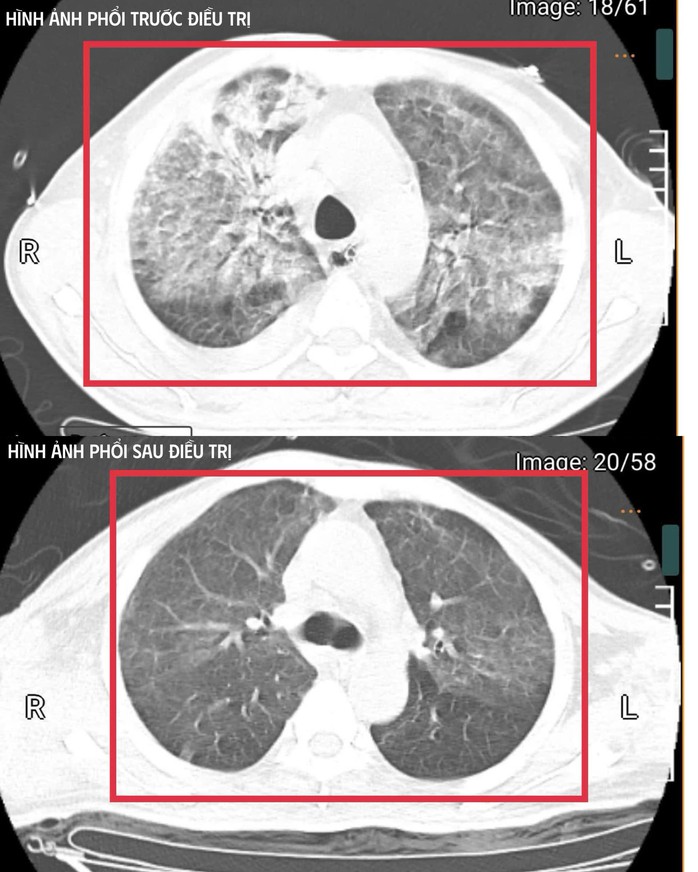

Phổi của bệnh nhân trước và sau điều trị

Sau ba ngày hồi sức, bệnh nhân bắt đầu cắt sốt, các chỉ số viêm giảm, huyết áp ổn định hơn, chức năng gan thận cải thiện, tri giác phục hồi. Trong ba tuần điều trị, bệnh nhân dần hồi phục, tập thở tự nhiên và hồi phục vận động.